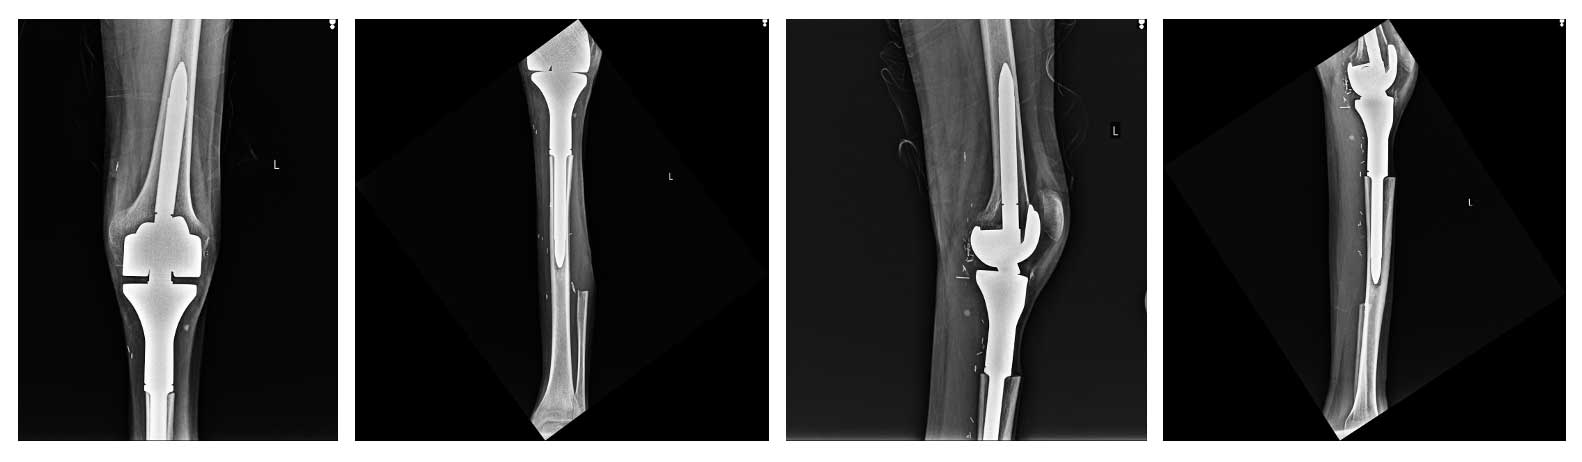

Ameliyat Sonrası: Röntgende proksimal fibula ve tibia rezeksiyonu sonrası tümör protezi uygulanımı görülmekte.